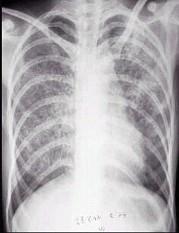

问题 男性,19岁,劳累后出现持续高热,体温39℃,无寒战,干咳、无痰,伴乏力、食欲减退,无呼吸困难,查体无阳性体征。血常规WBC:7.9×10/L,N 65%,血沉70mm/h,给予头孢呋辛及阿昔洛韦抗炎及抗病毒治疗10天无效。胸片见图。最有可能的诊断是 ( )

选项 A.急性肺脓肿 B.败血症 C.肺炎 D.伤寒 E.急性血行播散型肺结核

答案 E